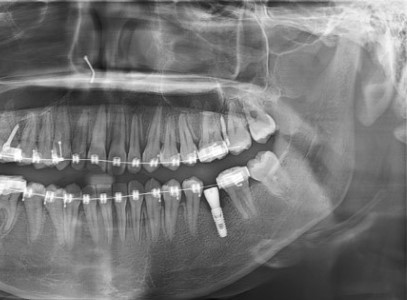

임플란트 공간 유지, 치아교정에서 꼭 필요한 이유 I 미금교정치과